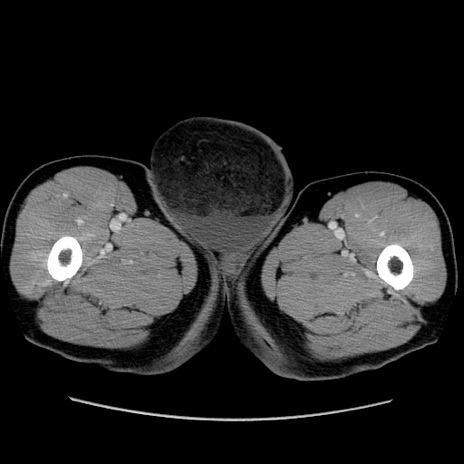

症例34(横断像)

【症例】60歳代 男性

【主訴】右鼠径部膨隆

【現病歴】1年程前より右鼠径部膨隆あり。自己にて還納可能だったため放置していた。3時間前より右鼠径部の脱出を認め、還納困難となり受診。

【既往歴】高血圧

【身体所見】右鼠径部に小児頭大の膨隆あり。弾性硬であり、用手還納は困難。左鼠径部にも膨隆を認める。脱出はなし。